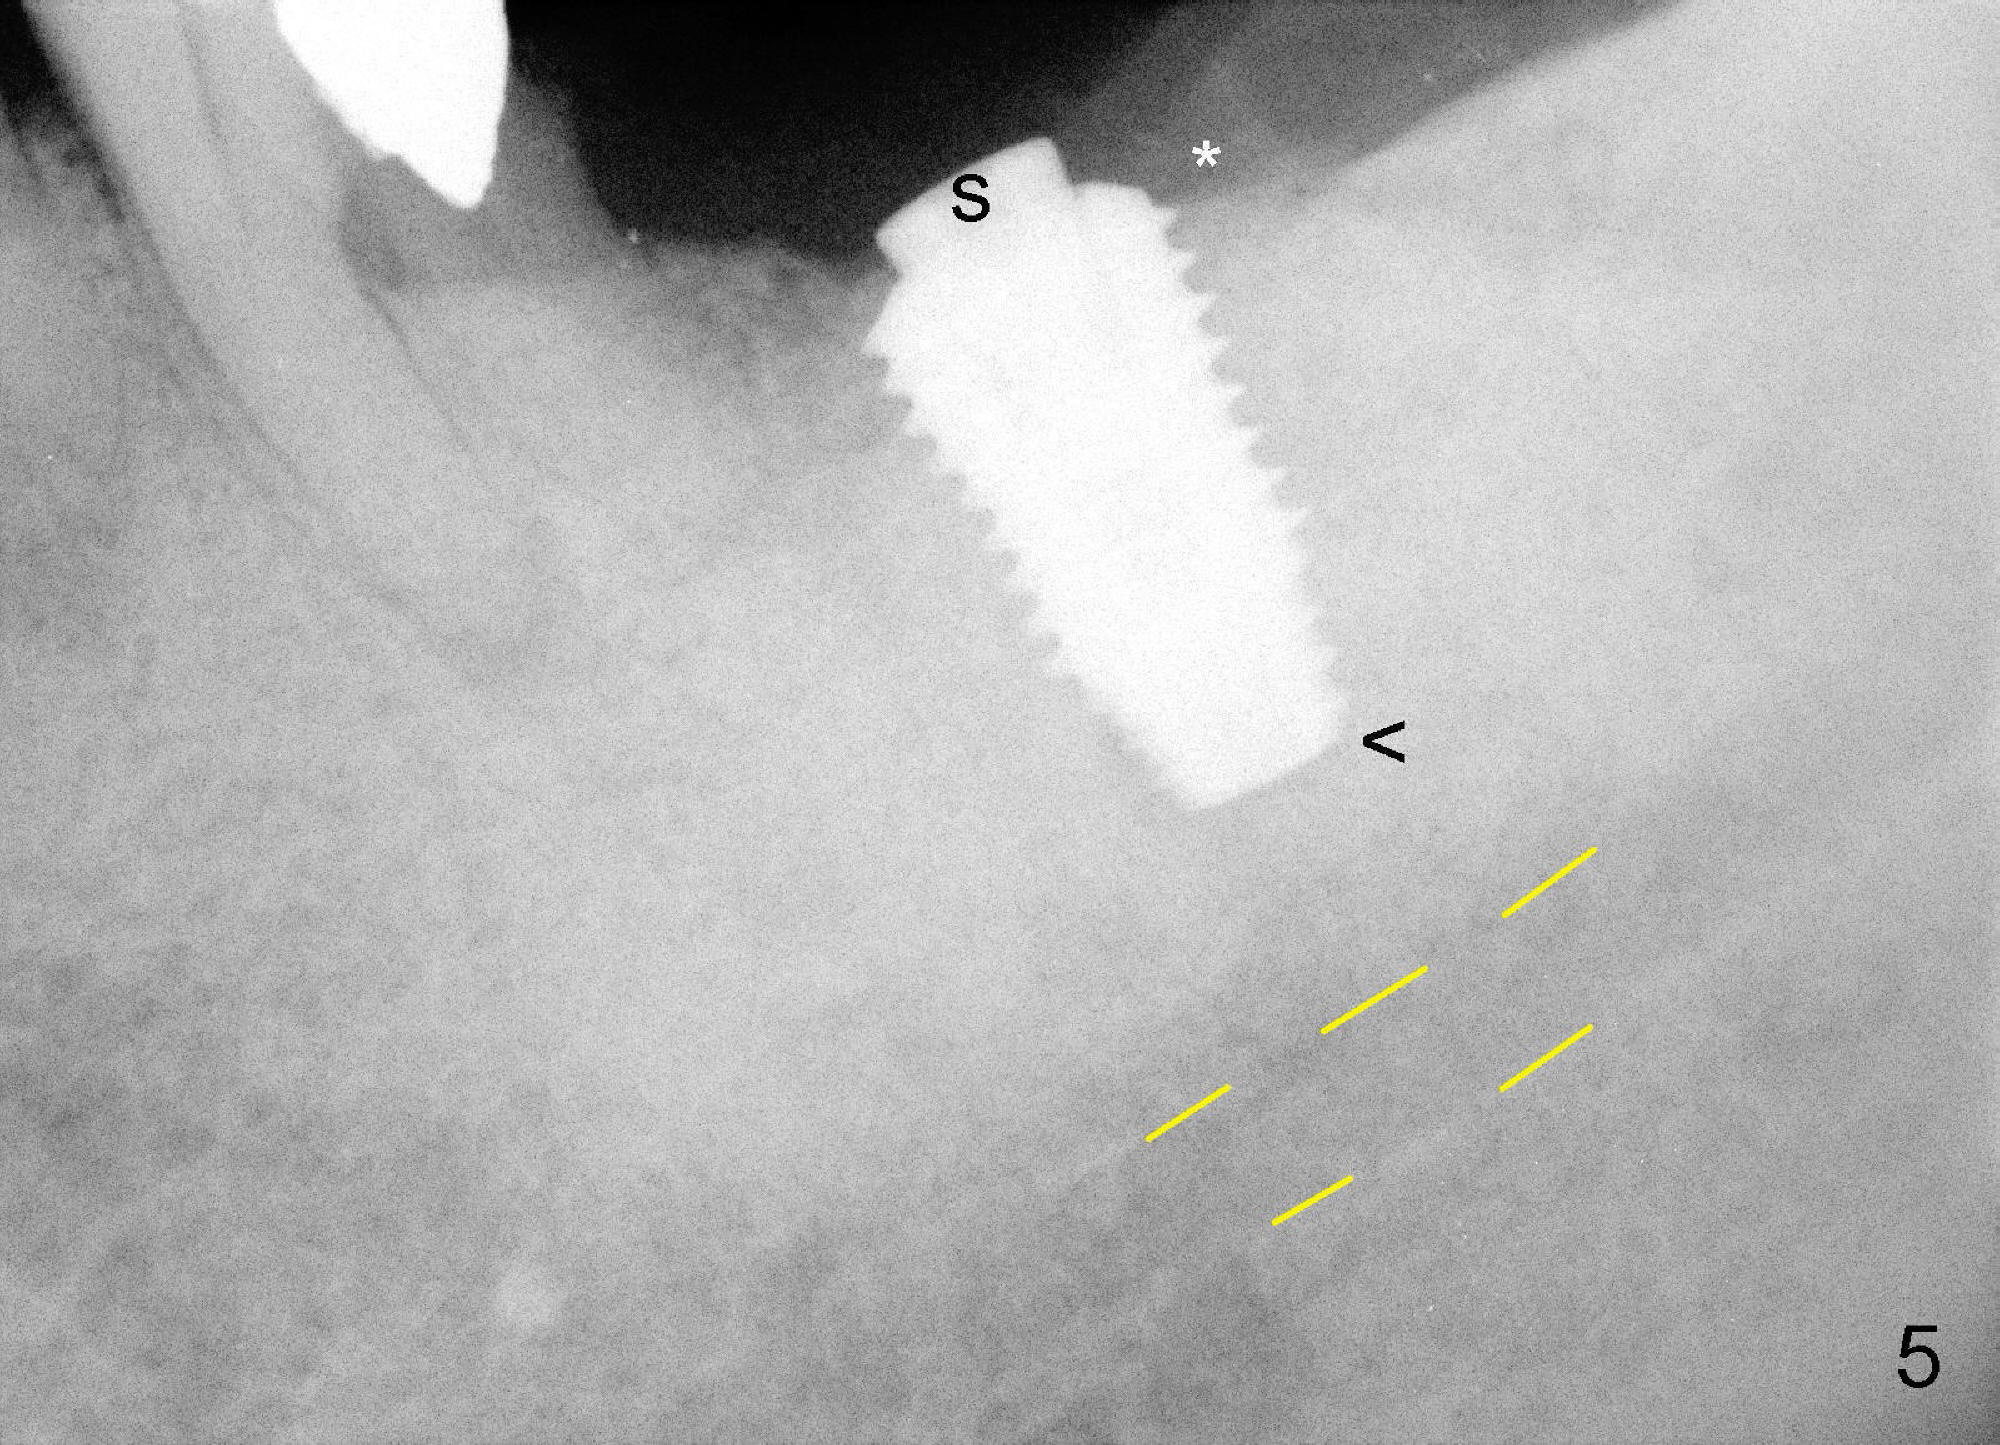

The implant is torqued down further (Fig.5 <, as compared to double ^ in Fig.2). The remaining distal exposed thread is covered by autogenous bone harvested during osteotomy (*). The graft is then covered by collagen dressing, which is held in place by a partially placed healing screw (S). The wound is closed by 4-0 Chromic gut suture and perio glue. The patient is instructed to continue oral Amoxicillin and Chlorhexidine mouth rinse postop.